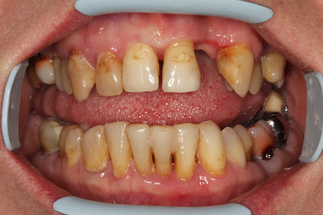

В основной группе 2 на фоне проводимого комплексного лечения с использованием геля «Метрогил-дента» отмечали улучшение как субъективных, так и объективных проявлений заболевания: уменьшались болезненность и кровоточивость десен, галитоз. Через 30 дней после лечения пациенты обеих групп отмечали значительное снижение болезненности, отека и кровоточивости десен, исчезновение неприятного запаха изо рта, некоторое снижение подвижности зубов, появление уверенности при жевании, улучшение общего состояния. При объективном обследовании отмечали уплотнение десневого края за счет уменьшения отека, существенное улучшение гигиенического состояния полости рта, прекращение выделения экссудата из пародонтальных карманов (Рисунок 13).

| до лечения | через 30 дней после лечения |

| Рисунок 13. Динамика состояния тканей пародонта у пациента с ХГП тяжелой степени через 30 дней после комплексного консервативного лечения с местным применением препарата «Метрогил-Дента» . | |